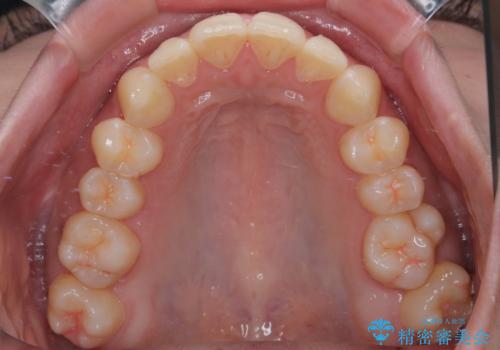

診察してみると、下の前歯が並ぶためのスペースが足りないことが、歯並びがデコボコしている原因でした。

そこで今回は、以下の2つの方法を組み合わせて治療を行いました:

下の前歯の歯と歯の間をわずかに削ってスペースを作る(IPR)

奥歯を後ろに動かして、前歯が並ぶためのスペースを確保する

この計画により、デコボコだった下の前歯はしっかりと並び、わずか1年で治療を終えることができました